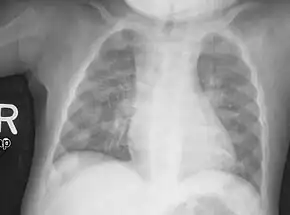

Rachitic rosary on chest radiograph |

The prominent knobs of bone at the costochondral joints of rickets patients are known as a rachitic rosary or beading of the ribs. The knobs create the appearance of large beads under the skin of the rib cage, hence the name by analogy with the beads of a Catholic Christian rosary.[1]